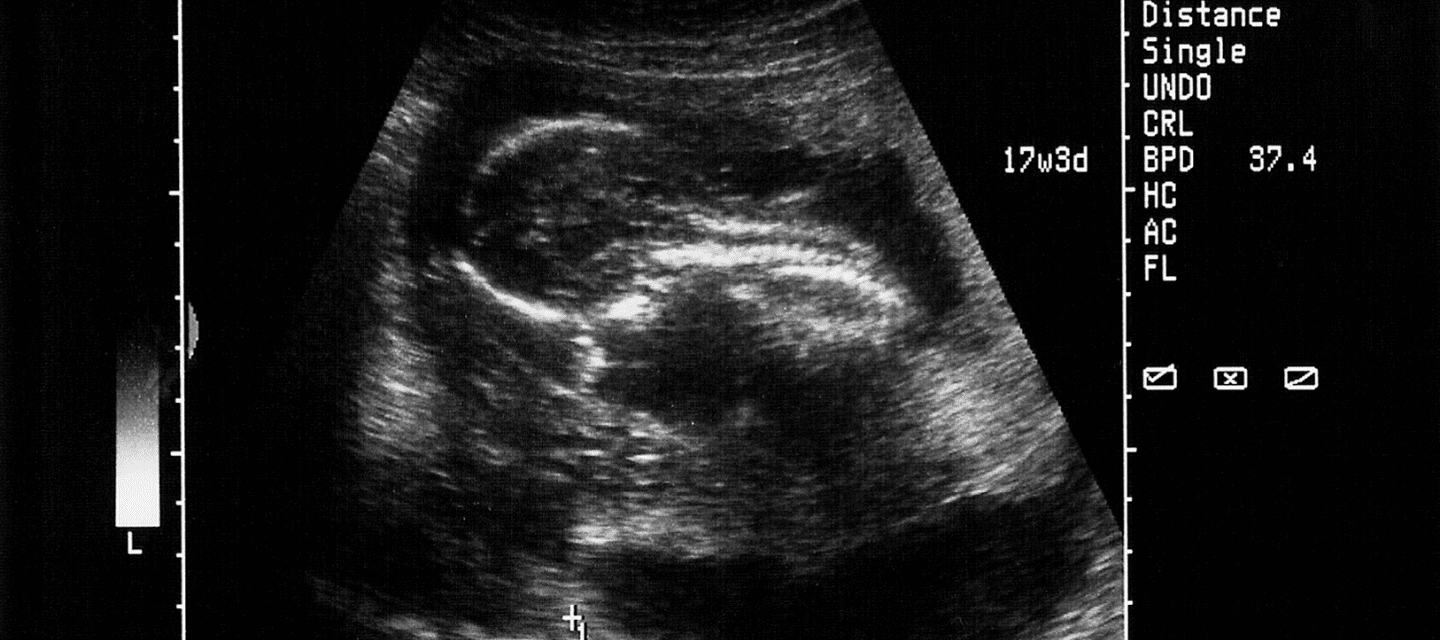

- Erste offizielle Ultraschalluntersuchung